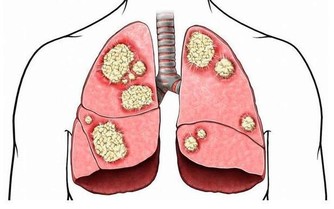

真菌感染:有毛癬菌所致的股癬、甲癬、足癬和手癬;有念珠球菌所致的口炎、陰道炎、巴氏腺炎,同樣也是好好壞壞難以根治。